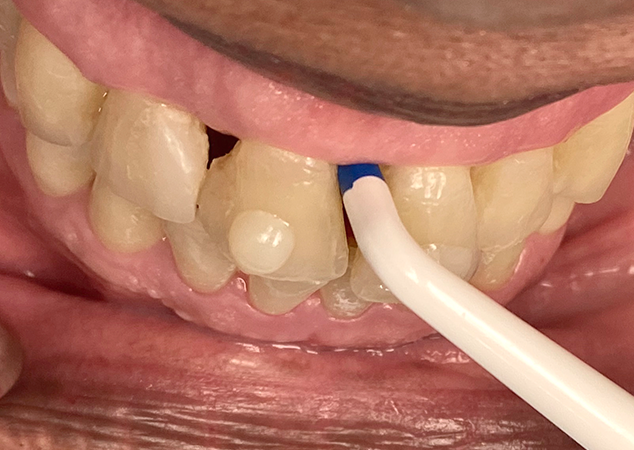

Lors de la consultation initiale, il est important de mesurer les embrasures gingivales à l'aide de la jauge de triangle noir Bioclear (Fig. 4). Ensuite, effectuez un essai de matrice pour évaluer l'exactitude de la mesure et la sélection ultérieure de la matrice destinée à combler l'embrasure (Fig. 5). L'expérience du clinicien et un œil attentif à l'esthétique guident la sélection finale de la matrice la mieux adaptée pour recréer le profil d'émergence approprié. Dans ce cas, nous avons convenu avec le patient de combler les embrasures de 13 à 23 et d'utiliser des matrices de triangle noir Bioclear pour réaliser des facettes à 360° afin de remodeler et de reconstruire les profils faciaux et incisaux.

FIG. 4A

FIG. 4B

FIG. 4C

Lors de la consultation initiale, la correspondance des teintes est obtenue à l'aide de pastilles de composite placées et polymérisées sur la surface vestibulaire des incisives centrales. Chaque embrasure est mesurée et enregistrée à l'aide de la jauge à triangle noir Bioclear.